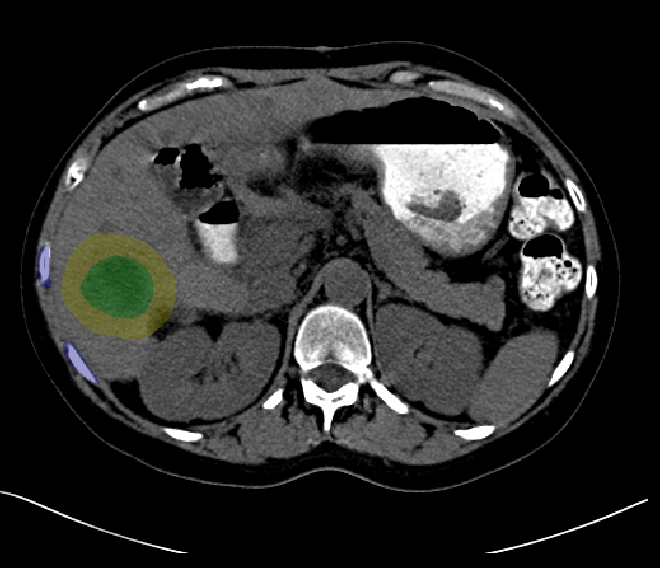

Liver RFA, segmentation after tumor has been dilated to include ablation margin.

| current | 16:38, 11 June 2009 | 660 × 568 (161 KB) | ZivYaniv (talk | contribs) | Liver RFA, segmentation after tumor has been dilated to include ablation margin. |